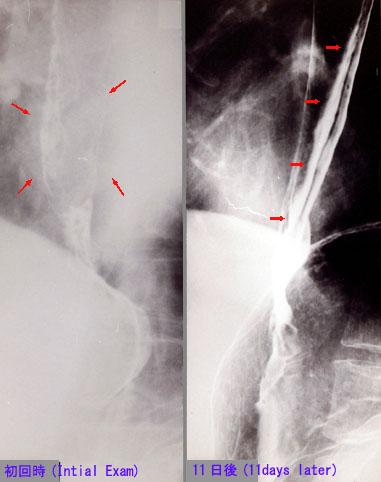

症例提示(所在地,施設名等): 東京都・ 国立がんセンター中央病院と九州がんセンターの共同作成

TIC症例

疾患(病理主体)の分類炎症性・潰瘍性疾患/その他

部位(臓器別)食道/下

検査方法X-P

病変の最大径(ミリ)40以上